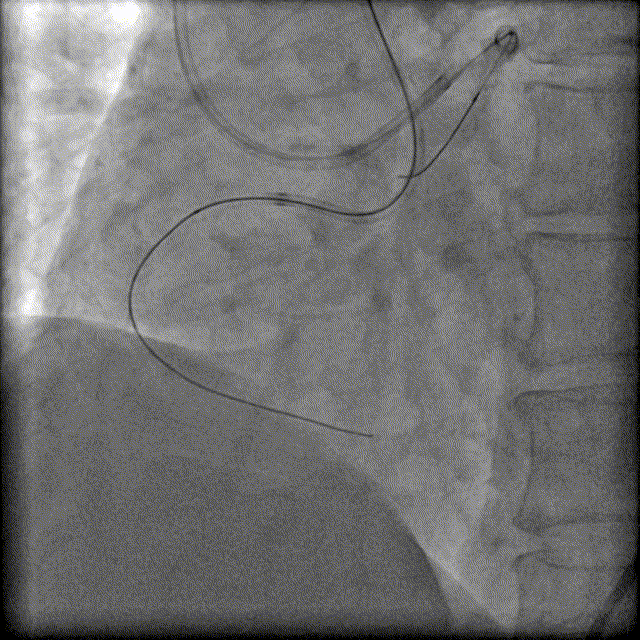

换用Instantpass微导管(170cm)支撑下送Fielder XT-R导丝通过LAD-RCA心外膜侧枝逆向通过RCA闭塞病变,推送微导管后交换Gaia Third导丝,RCA正向送Telescope™导引延长导管进行主动迎接Gaia Third导丝。

建立轨道后,交换为Runthrough 导丝后,行IVUS检查证实导丝位于血管真腔。

利用IVUS精确选择支架落脚点。